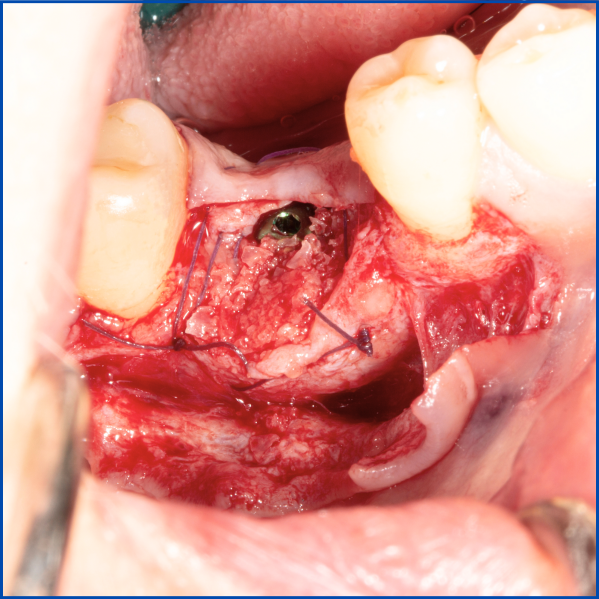

Kist nedeni ile çene kemiğinde defekt oluşmuş vakamıza sert ve yumuşak doku ogmentasyonu uyguladık.